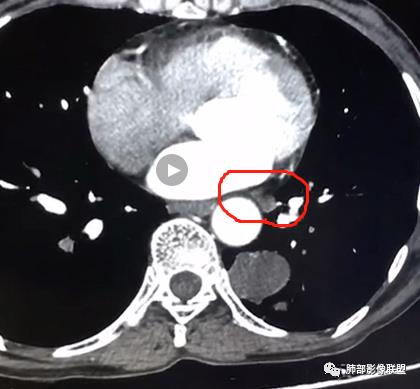

隔离常规是要考虑的,我需要看到供血血管

如果明确不是体循环供血

隔离肺

膈下的体动脉供血

体循环供血

融合,隔离肺。。

这种常规来说,供血血管是非常清晰的。

就是一个体循坏的膈下的供血,我为什么考虑先天性的,我觉得左下肺是变小的。

我担心的是有些恶心肿瘤的,它也可以是体循坏供血。

但是这么明显的少,放个待排吧,首先选择隔离征吧。

结果还是:肺隔离症

这个病理结果结合影像,有明显的体循环动脉供血血管进入病灶,诊断隔离肺 没问题